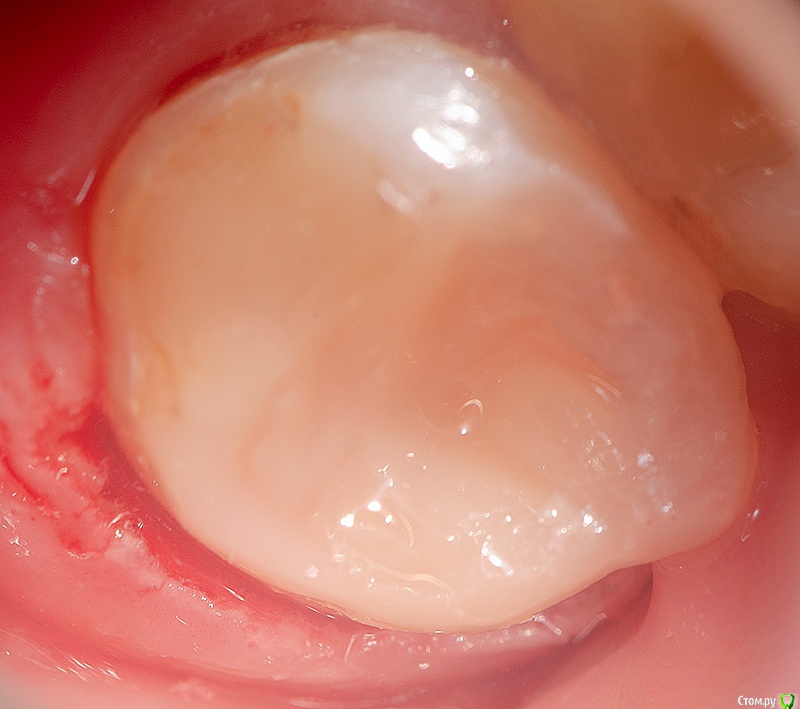

Romanson Опубликовано 9 февраля, 2019 Поделиться Опубликовано 9 февраля, 2019 Всем приветВерхний восьмой, который успел сместиться на место 7.Жутко утомляют такие зубы1. Убрал кариес2. Коагулировал десну3. Накинул платок4. Протравил границу5. Нанес адгезив6. Восстановил стенку жидким Каков Ваш протокол в таких зубах?Как избежать подтекания в таком случае?Какой материал можно использовать для стенки, чтобы подтекание было не критично? 3 Ссылка на комментарий

Turalyon Опубликовано 4 ноября, 2019 Поделиться Опубликовано 4 ноября, 2019 Всем приветВерхний восьмой, который успел сместиться на место 7.Жутко утомляют такие зубы1. Убрал кариес2. Коагулировал десну3. Накинул платок4. Протравил границу5. Нанес адгезив6. Восстановил стенку жидким 1.jpg2.jpg3.jpg Каков Ваш протокол в таких зубах?Как избежать подтекания в таком случае?Какой материал можно использовать для стенки, чтобы подтекание было не критично? Я в подобных случаях от десны поднимаю витремером, если зуб в окклюзии то поверх композитом. 1 Ссылка на комментарий